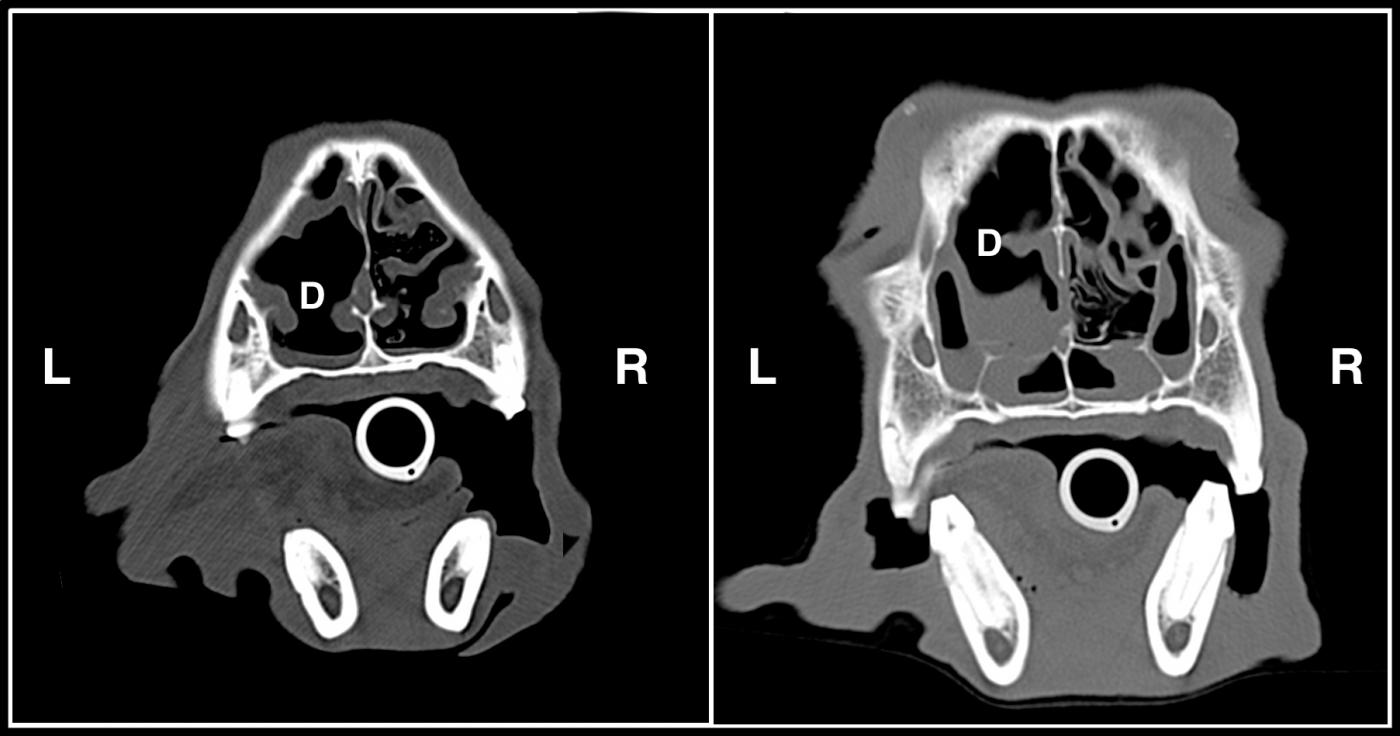

From criticalcaredvm.com

Aspergillosis in Dogs A Destructive Sinus & Nasal Disease Nasal Discharge Dog Differentials Nasal discharge is a clinical sign, rather than a disease. nasal disease in the dog generally presents with a combination of discharge, sneezing, epistaxis, stertor and gagging. the most common local causes of nasal discharge in dogs besides cancer are allergic rhinitis, foreign bodies (such as plant material), fungal. As such, it may be associated with numerous causes.. Nasal Discharge Dog Differentials.